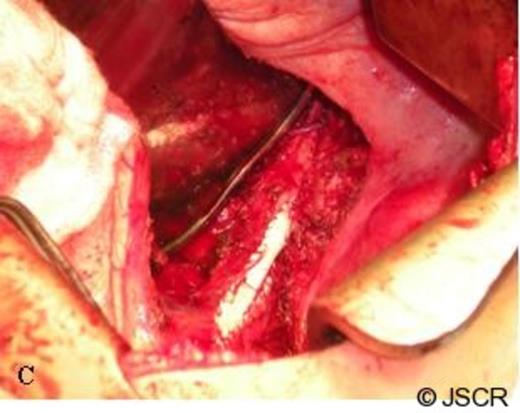

Following careful dissection of the posterior ligamentous attachments of the IVC to the liver, a Satinsky vascular clamp was placed and a 1 cm x 1 cm x 0.5 cm portion of the IVC was excised. The entire specimen was removed en bloc (Figure 2) consisting of diaphragm, right adrenal metastasis measuring 6 cm x 4 cm x 3 cm, a scant amount of normal adrenal tissue, the small patch of IVC and the right adrenal vein which was completely encased by tumor. A patch angioplasty of the IVC was then completed with a PTFE patch and sewn in with a running 5-0 Prolene suture (Figure 3). The diaphragm was closed primarily with pledgeted 1-0 Ethibond mattressed sutures, two 28-French chest tubes were placed through separate stab incisions, and the lung was re-expanded under direct vision. The patient tolerated the procedure well and was discharged home on post-operative day 8.

The en bloc specimen with the IVC surface in the foreground and the left adrenal vein clearly visible (arrow).